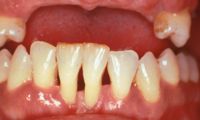

Este paciente se presentó con la queja principal de incomodidad en el funcionamiento de los dientes anteriores inferiores. Nótese la pérdida y recesión de encía.

La evidencia clínica de una enfermedad periodontal grave fue respaldada por las pruebas radiográficas en las que se observa una pérdida de hueso de más del 70% en los incisivos mandibulares y la presencia de un grado de movilidad 2 para los cuatro incisivos.

La queja principal de este paciente era la incomodidad durante el funcionamiento de los dientes anteriores inferiores. Nótese la pérdida y recesión de encía. Todos los incisivos tenían grado 2 de movilidad.

Otro factor que complicaba el caso fue que el paciente había completado dos años de tratamiento de ortodoncia para cerrar el espacio que existía en anteriores debido a la pérdida de un incisivo central por enfermedad periodontal. Hay evidencia radiográfica de pérdida de masa ósea de más del 70% en el incisivo central restante.